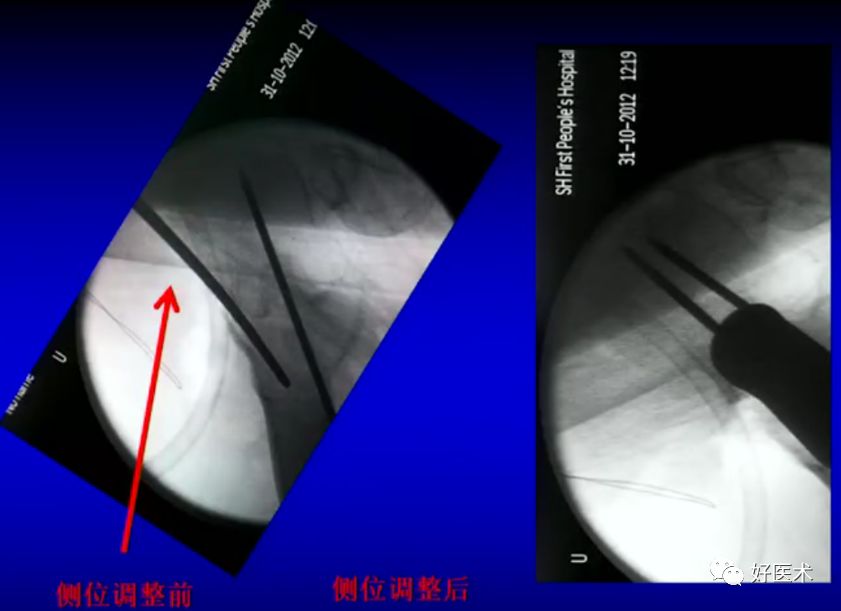

6.正确的股骨颈正侧位

侧卧位如何透股骨颈的侧位:

-

标准侧位

球管20-30°

侧卧位行转子间骨折固定